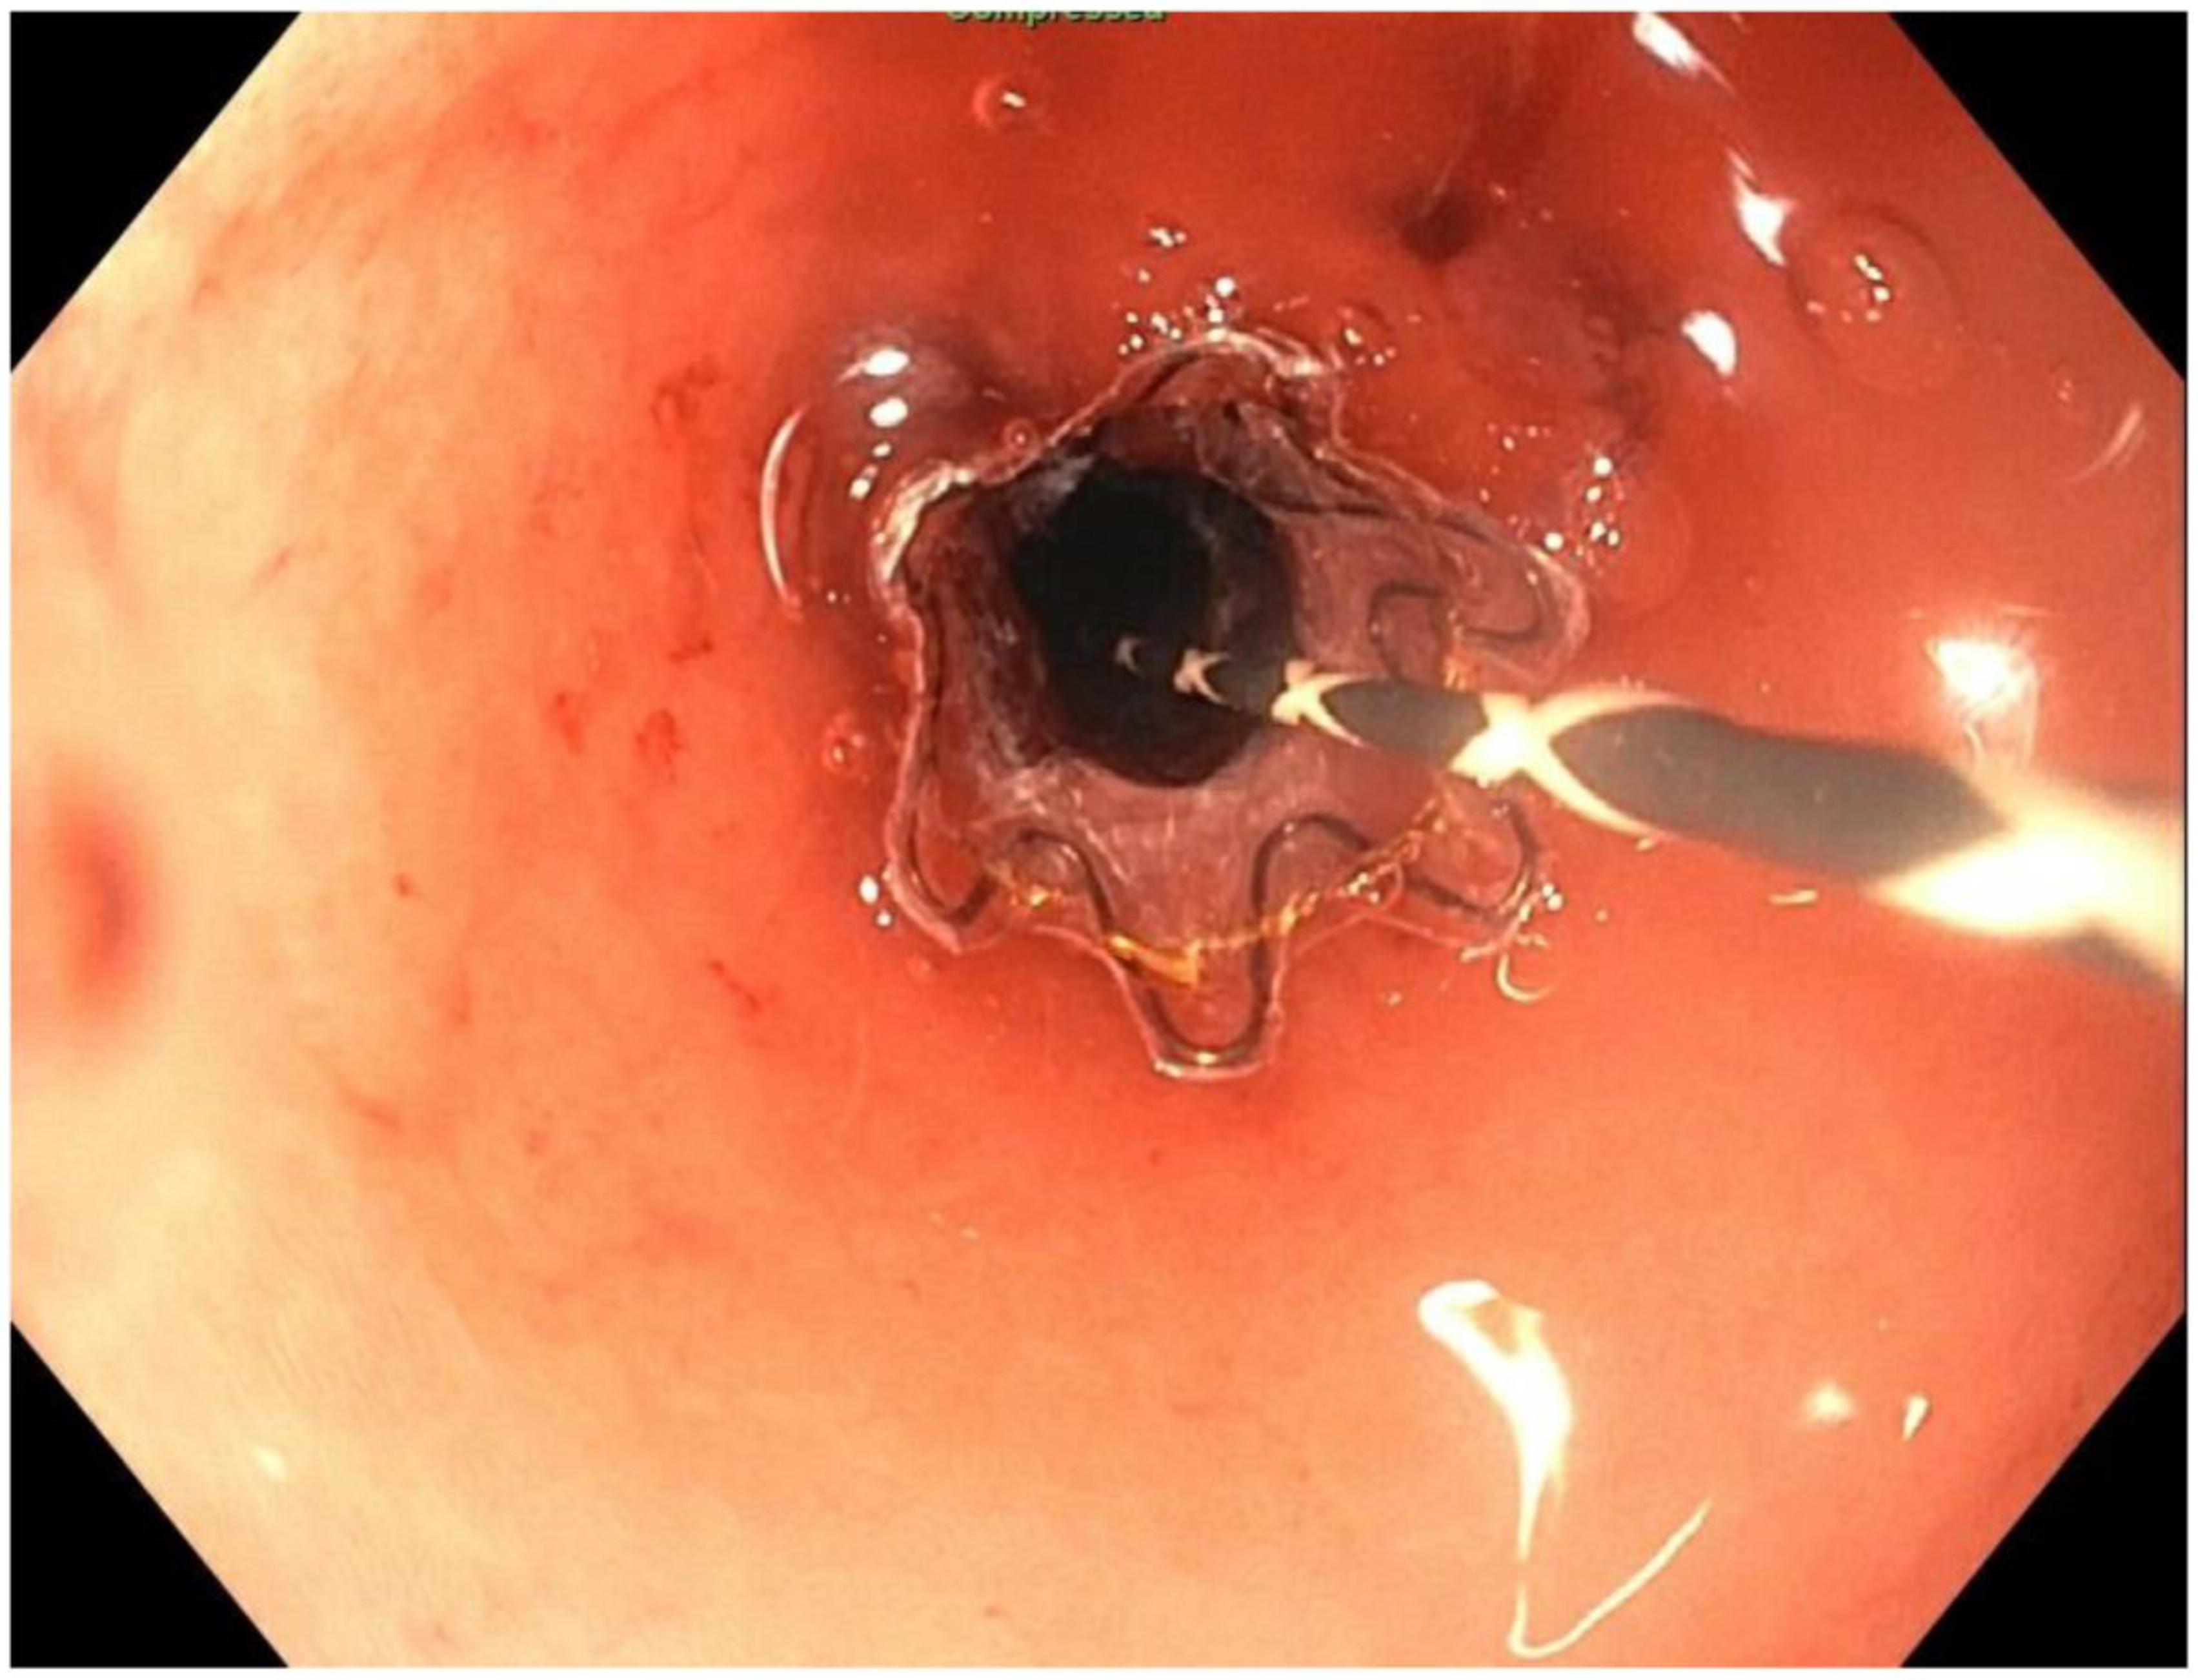

2. Detailed Case Description